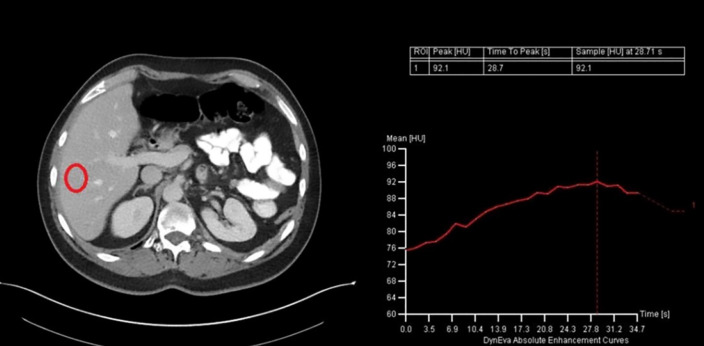

Objectives: to determine (1) a target Hounsfield unit (HU) for portal venous phase iodinated contrast media enhanced abdominal CT scans, (2) an equation for a personalized total contrast agent volume, and (3) the best/most appropriate time between injection and plateau/peak in HU enhancement. Material and methods: from an original dataset of 5,000 cases, a weight representative subset of 370 cases was sampled for detailed HU measurements. An additional 90 cases were used for visual grading to define the minimal HU required for diagnostic quality, which led to the proposed target HU. This study uses the fact that in a first approach, the injected contrast agent volume and HU correlate linearly. Based on the injected contrast agent volumes and HU measurements in the patient scans, it was then calculated which (ideal) volume would have reached the target value. The ideal volumes and patient data (weight, height, heart rate, age, and gender) were correlated by means of a regression analysis, to determine a new patient-specific contrast volume calculation equation. The best scan delay time was derived from the start of the injection to the HU enhancement plateau/peak evaluated from manually triggered venous phase scans. Results: The target HU value was 125. This can be achieved with a personalized contrast agent volume (ml), equal to - 108.5 + ∗ weight(kg) + 0.40 ∗ heart rate(bpm) + 0.61 ∗ height(cm). The time delay between injection and HU plateau/peak was found to be, on average, 102 s. Conclusion: this study proposes a comprehensive protocol for contrast enhanced venous phase scans, including a target HU, a personalized contrast volume, and a scan delay.